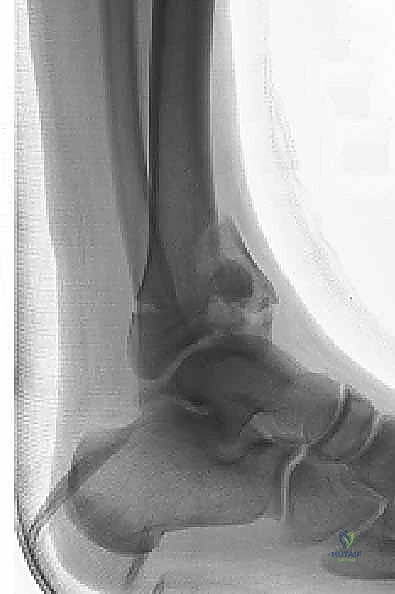

1. التصوير بالأشعة السينية التقليدية (X-Rays)

يتم أخذ صور من ثلاث زوايا (أمامية خلفية AP، جانبية Lateral، ومورتيس Mortise). تعطي هذه الصور فكرة عامة عن نمط الكسر، قصر الساق، ومدى انزياح العظام.